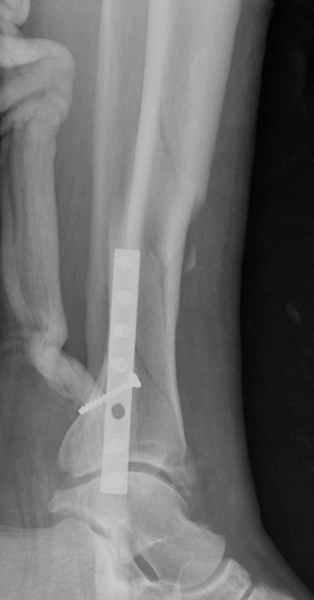

Здесь мы использовали новый Synthes Nail с дополнительными дырками, в проксимальной части 4: по две косых и поперечные (один стандартный а другой динамический), в дистальной части две поперечные, прямая и косая. Вес больного более 120 кг, нагрузку начнем через месяц.

Получилось красиво, поздравляю. Вверху можно было ограничиться одним винтом во фронтальное статическое отверстие, зачем два 45-градусных?

При такий спирали задний край tibia может быть сломан - нет ли этого в данном случае? На всякий случай можно было ввести 1-2 винта 4,5 мм спереди назад мимо гвоздя. Хотя самый дистальный блокирующий винт, возможно, зацепил этот отломок. А какой тут диаметр гвоздя и locking винтов?

Если там и правда сломан задний край, то лучше с нагрузкой подождать, даже будь больной полегче.